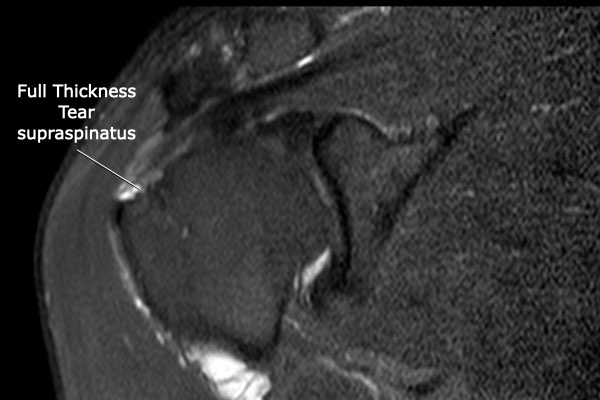

Rách toàn bộ chiều dày hoàn toàn

Nhấp vào hình ảnh để phóng to, sau đó cuộn qua các lát cắt.

Có hình ảnh rách toàn bộ chiều dày gân cơ trên gai kèm co rút và teo cơ.

Lưu ý các dải mỡ trong cơ tròn bé, cơ trên gai và cơ dưới gai.

Đo kích thước tổn thương rách toàn bộ chiều dày của chóp xoay theo hai chiều.

Teo cơ – Dấu hiệu tiếp tuyến (Tangent sign)

Phương pháp đánh giá teo cơ của Warner dựa trên hình ảnh mặt phẳng chéo đứng dọc (oblique sagittal) ở vị trí trong so với mỏm quạ.

Một đường thẳng được vẽ từ bờ mỏm quạ đến đỉnh dưới của xương bả vai, và từ gai xương bả vai đến mỏm quạ.

Nếu cơ lồi lên trên đường này, không có teo cơ.

Nếu cơ nằm ngay dưới đường này, có teo cơ mức độ vừa.

Nếu hầu như không thấy cơ, có teo cơ mức độ nặng.